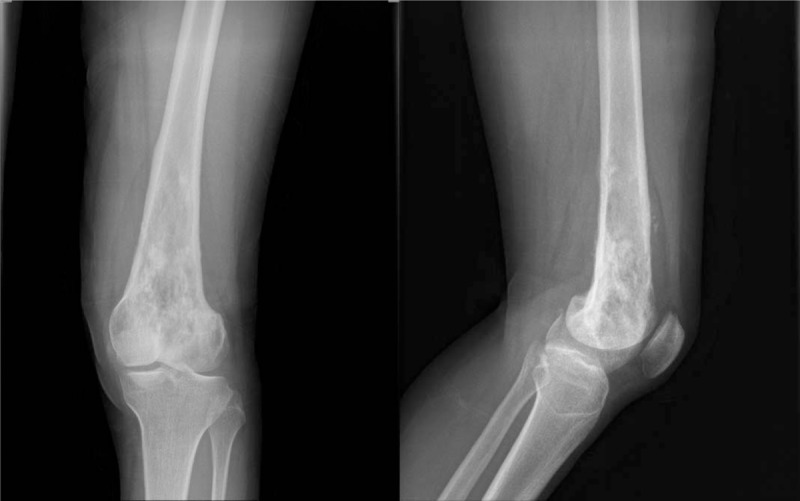

Radiografía

Lesión lítica expansiva, márgenes variables, adelgazamiento cortical. La agresividad radiológica obliga a ampliar diferencial.